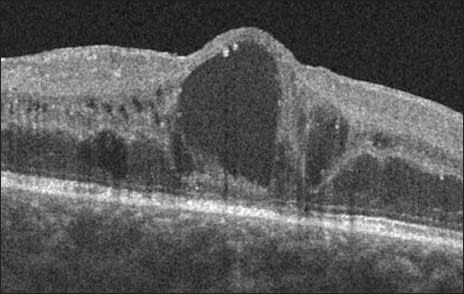

Upon examination, the laser-treated left eye had minimal edema but was the worse-seeing eye (20/80−2) due to laserinduced scotomas. The patient was very unhappy about her decreased vision and had refused subsequent laser treatment in the other eye because of her dissatisfaction. In the dominant right eye, optical coherence tomography (OCT) and fluorescein angiography (FA) revealed clinically significant macular edema (Figs 1, 2). Central retinal thickness was 326 µm and visual acuity (VA) was 20/50−1.

Figure 1. Pre-MicroPulse Laser Treatment: SD-OCT (Spectralis) CSDME Right Eye. Central retinal thickness: 326 μm.